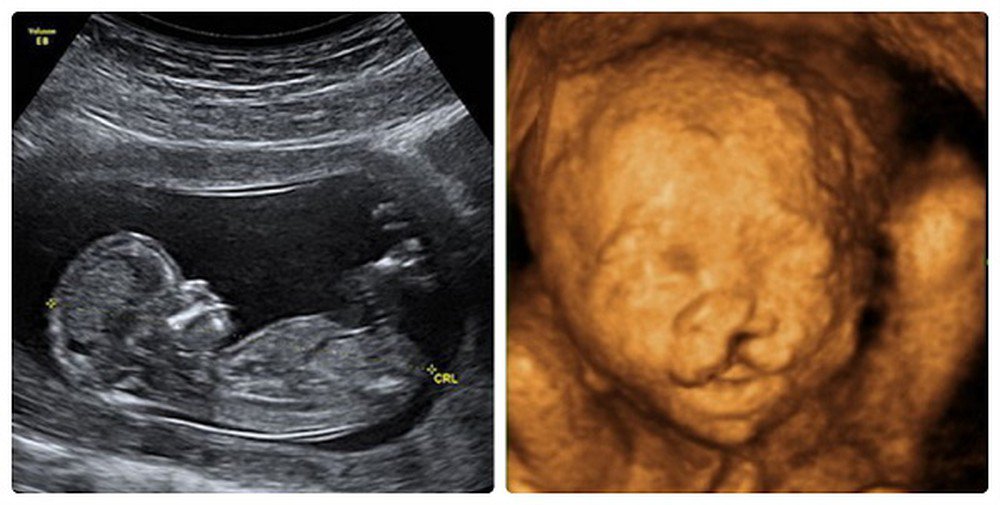

Hở hàm ếch sẽ diễn ra song song cùng với thời kỳ phát triển của thai nhi và trở thành dị tật nên các bậc phụ huynh cần hiểu rõ hơn về bệnh lý này. Mời bạn đọc theo dõi bài viết dưới đây!

Hở hàm ếch là tình trạng các mô của miệng hoặc môi không hình thành thích hợp trong quá trình phát triển của thai nhi. Đây chính là một dị tật bẩm sinh vùng mặt làm biến dạng khuôn mắt của trẻ.

Môi là bộ phận được hình thành vào giữa tuần lễ thứ 4 và thứ 5. Vào khoảng giữa tuần thứ 7 và thứ 8 của thai kỳ sẽ hình thành hàm trên. Nên ở thời điểm này các yếu tố bên ngoài có thể gây tác động xấu đến phụ nữ mang thai và gây ra các dị tật thai nhi như hở hàm ếch.